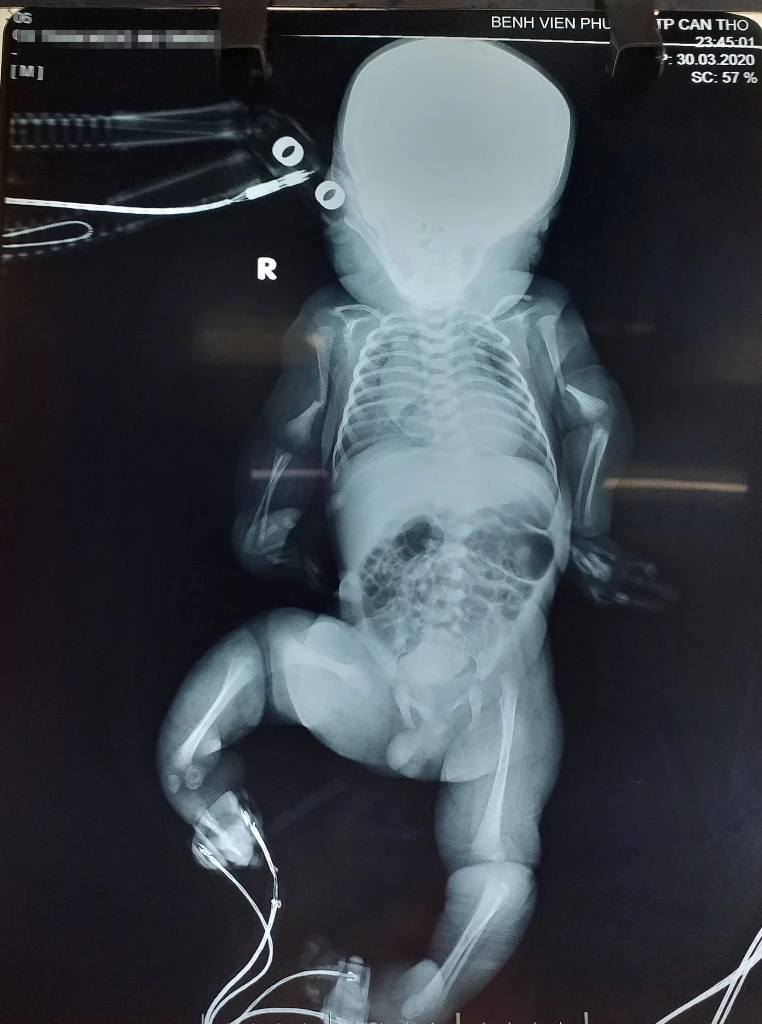

Hình ảnh chụp X-Quang của em bé sơ sinh nghi bị bệnh xương thủy tinh. Ảnh do BV cung cấp.

Các hình ảnh điển hình trên X-quang cho thấy xương tứ chi biến dạng, vỏ xương mỏng, giảm độ đặc của xương, gãy xương tự nhiên. Với các hình ảnh đặc hiệu trên, các bác sĩ chẩn đoán ban đầu nghi ngờ bé mắc bệnh xương thủy tinh (Osteogenesis Imperfecta).

Ngày 10-4, Bệnh viện (BV) Phụ sản TP Cần Thơ cho biết ngày 30-3, khoa Cấp cứu của BV tiếp nhận thai phụ TNN (29 tuổi, ngụ tỉnh Vĩnh Long) nhập viện trong tình trạng chuyển dạ sanh, ối vỡ sớm, thai 38 tuần, vết mổ cũ và được chỉ định mổ lấy thai. Em bé cân nặng 2.480 g, tứ chi có biến dạng.